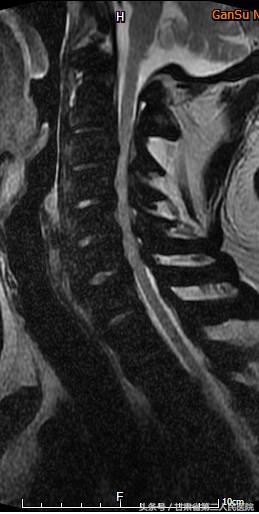

入院后行全脊柱X线、CT及MRI示:C3-6颈椎后纵韧带骨化引起的脊髓型颈椎病,并有严重的石骨症。

术前